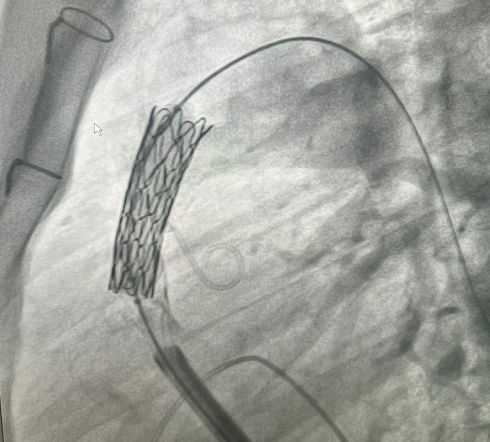

– Нам доступны клапаны с размерной линейкой от 2 до 3-х сантиметров. Клапан можно имплантировать, если размер выводного тракта и самого кондуита  – места, куда надо ставить клапан – от 2 до 3-х см. Если диаметр меньше, то клапан будет кальцинироваться, тромбироваться, створки перестанут работать и снова произойдёт стеноз, – пояснил рентгенэндоваскулярный хирург Михаил  Комиссаров.

У пациента из Луганской Народной Республики просвет ранее имплантированного кондуита составлял 1,5 сантиметра, поэтому рентгенхирурги на первом этапе расширили его методом баллонной дилатации. При этом был риск разрыва сосуда, поэтому, чтобы избежать возможных осложнений, медики сначала имплантировали стентграфт – металлический каркас, покрытый герметичным полимером. Просвет кондуита удалось расширить до необходимого диаметра. Затем через бедренную вену хирурги доставили к сердцу искусственный биологический клапан лёгочной артерии Myval индийского производства.

– Новый клапан прослужит несколько лет. Что особенно важно, в дальнейшем можно будет выполнить малоинвазивную процедуру имплантации клапана по технологии «стент в стент», – отметил заведующий кардиохирургической службой.